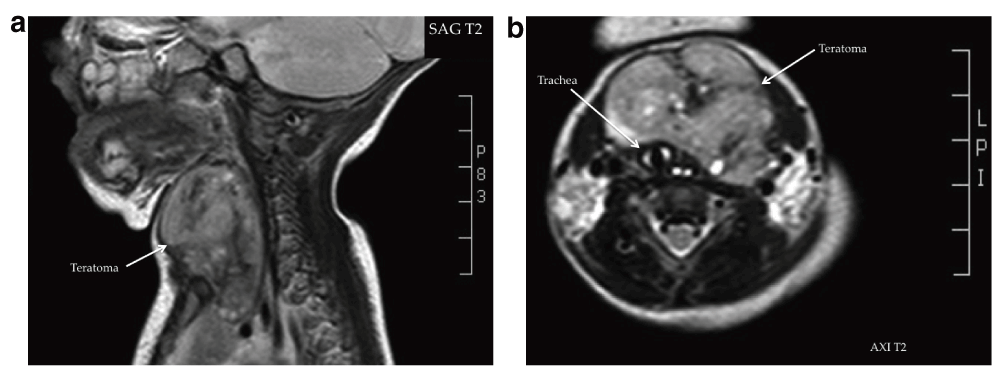

He was admitted to our pediatric intensive care unit 25 days after he had been discharged from the other hospital, and was immediately intubated. An X-ray showed a small amount of interstitial infiltrate, compatible with aspiration pneumonia. However, the respiratory distress was attributed mainly to an upper airway obstruction. It was difficult to tracheally intubate the infant; only an uncuffed 2.5 mm endotracheal tube (ETT) was able to be inserted into the trachea and it was difficult to place this in the right position. The X-ray after intubation showed the ETT in a high position and the trachea displaced to the right (Figure 2). Magnetic resonance imaging (MRI) revealed the extent of the cervical mass and its compression on the trachea, and the latter’s subsequent displacement (Figure 3a and 3b).

a. Sagittal MRI (T2) of the neck showing the teratoma. b. Axial MRI (T2) of the neck showing the teratoma and the tracheal displacement.